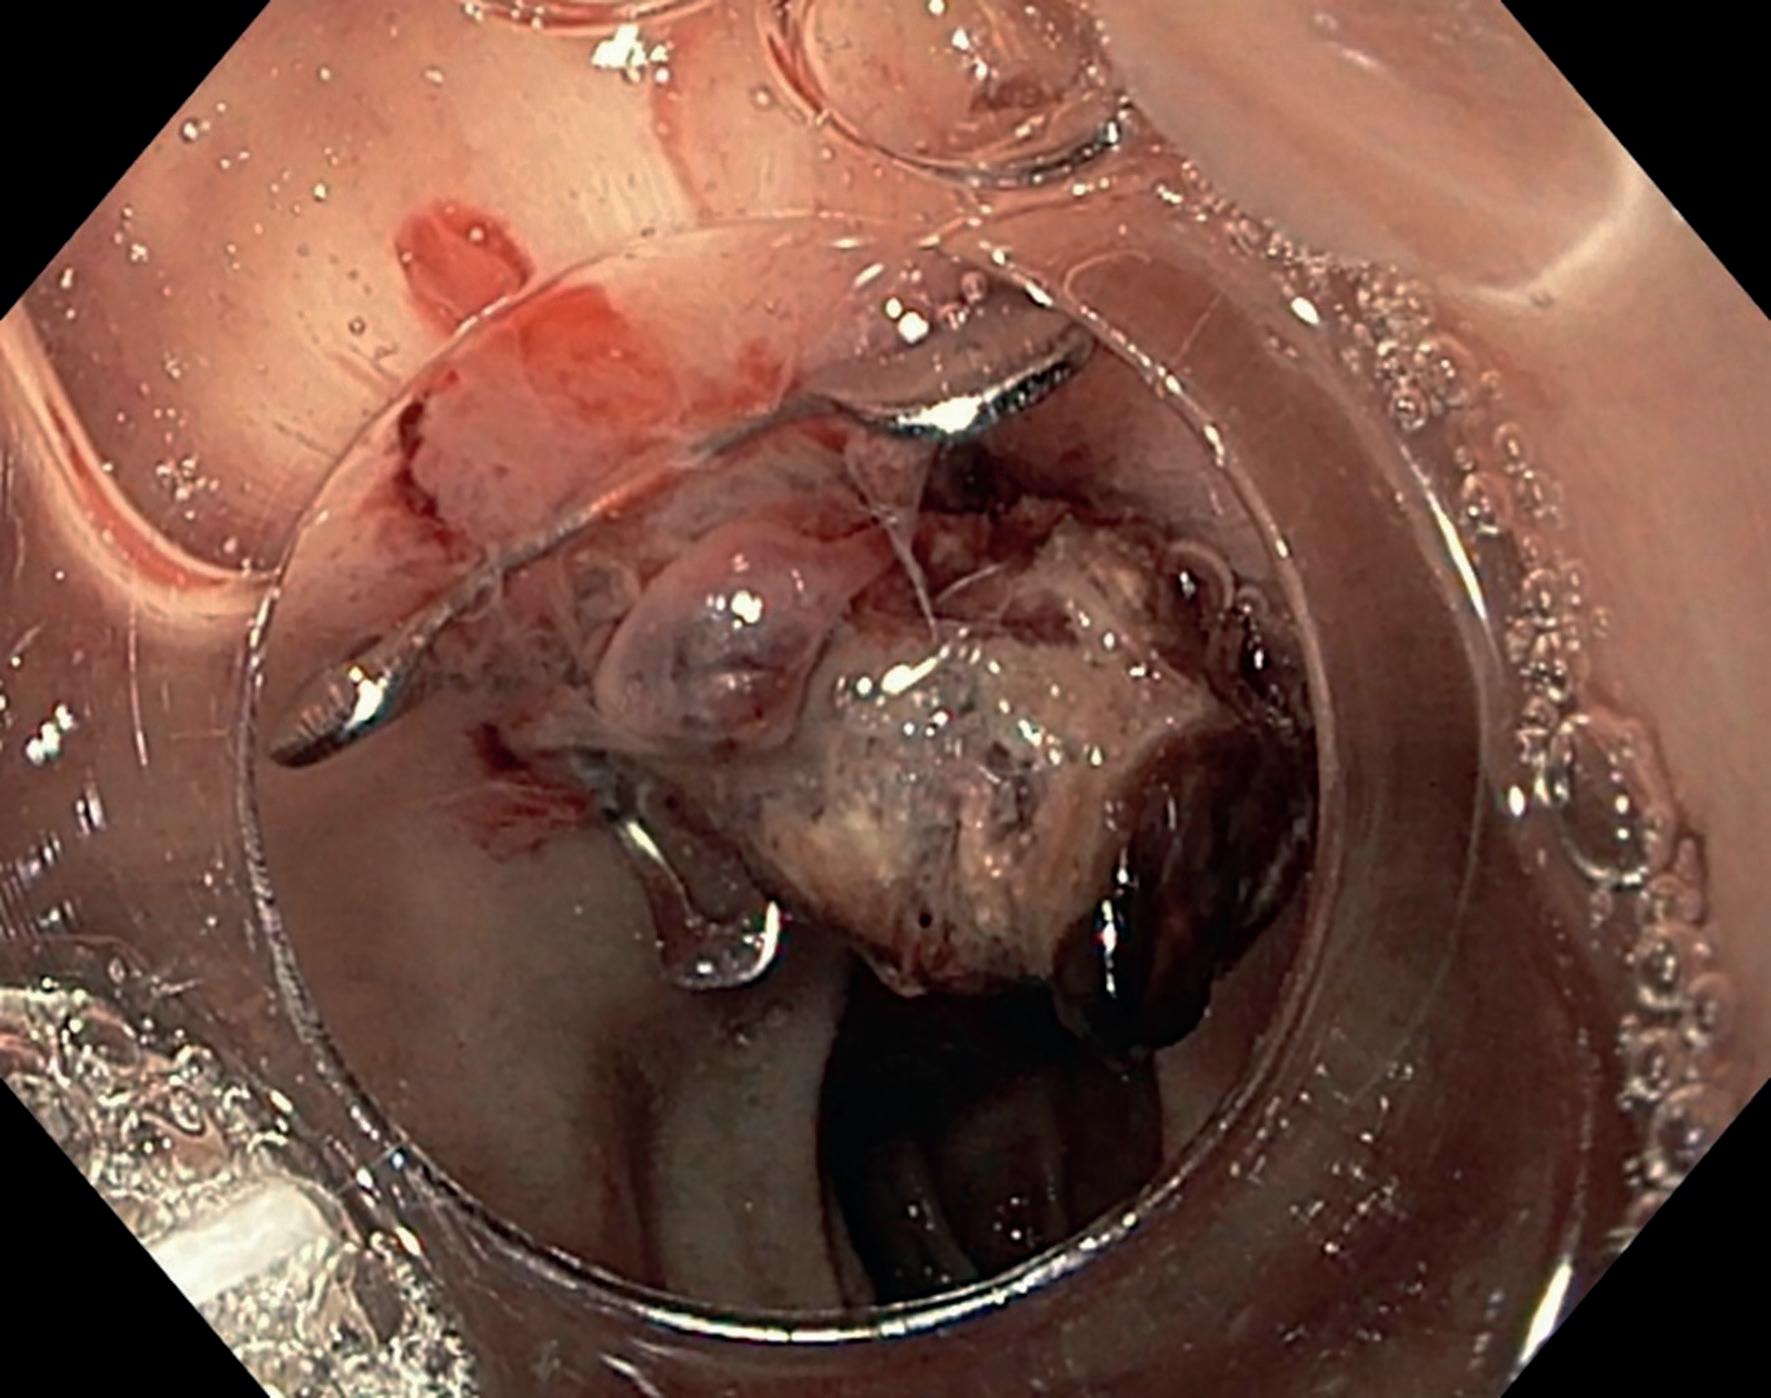

den må likevel behandles da lesjoner kan fortsette å vokse og skape skade lokalt. BCC-lesjoner er ofte gjennomsiktige med rosa, perlelignende nodul og med telangiektasier på overflaten (bilde 1 og 2). BCC klassifiseres som nodulære, mikronodulære, superfisielle, infiltrerende, morfea-type og basoskvamøse. De tre sistnevnte regnes som de mest aggressive, med høyest risiko for residiv og infiltrerende vekst.

Plateepitelkarsinomer kan variere mer i utseende, men starter ofte med en tørr, flassende flekk som etter hvert utvikler seg til et sår som ikke heles (bilde 3 og 4). De kan være flate eller store som et horn. I motsetning til BCC har 3-7 % av plateepitelkarsinomene metastasepotensiale (8). Aktinisk (solar) keratoser (AK) kan utvikle seg til plateepitelkarsinom. Det er vanskelig å vurdere risikoen for at en enkelt AK skal utvikle seg til plateepitelkarsinom, derfor anbefales det å fjerne AK.